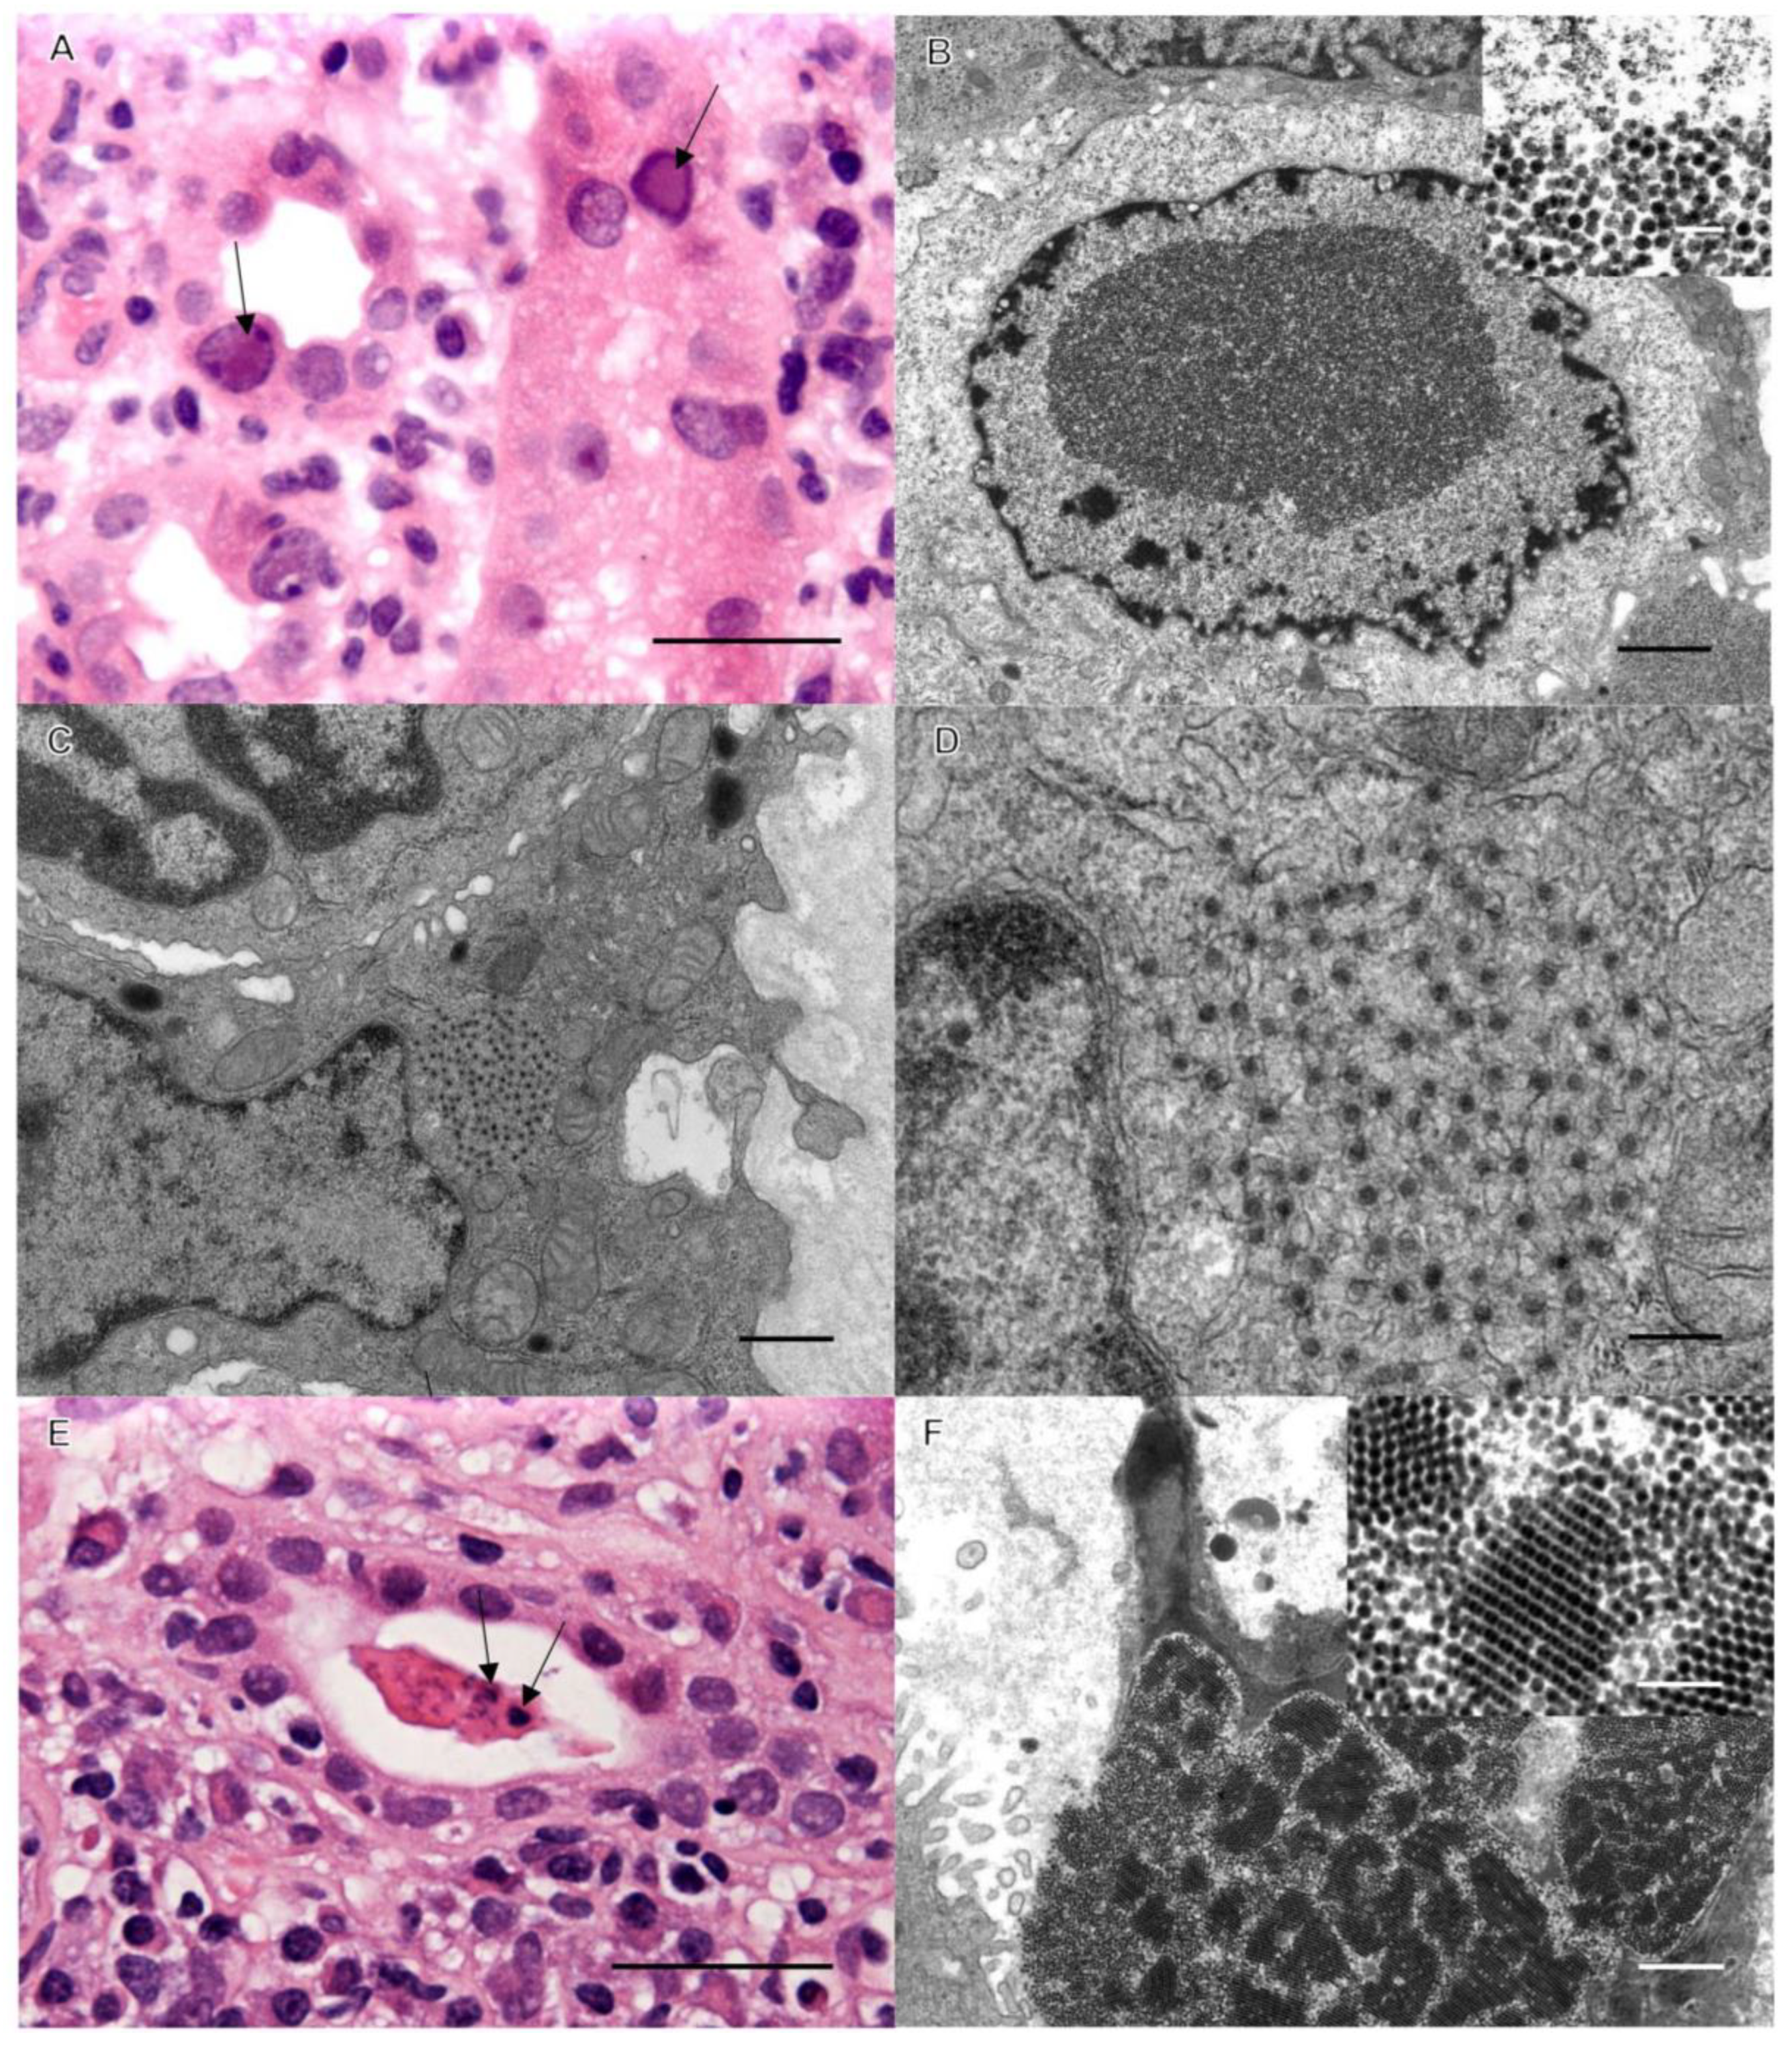

Case 1: Background. A 37-year-old male with end-stage renal disease (ESRD) secondary to Goodpasture syndrome received a deceased donor kidney transplant. His post-transplant status was excellent for 12 months, with blood urea nitrogen (BUN) and creatinine stable within normal ranges at 14 mg/dL and 1.12 mg/dL, respectively. His immunosuppression consisted of (Myfortic; also known as the generic drug CellCept) 360 mg of mycophenolate twice a day and 3 mg of tacrolimus twice a day. During a routine check-up, his creatinine and serum titers of BK virus were found to be elevated, and an assessment biopsy of his allograft was performed. Severe interstitial inflammation was observed, and immunohistochemistry (IHC) revealed that most of the lymphocytic infiltrates were CD3-positive; CD20 demonstrated moderately positive mononuclear cell aggregates, and CD19 and CD68 were occasionally positive. C4d was negative in interstitial capillaries, negating humoral rejection. Renal collecting tubules had prominent nuclear changes consistent with BK virus infection (Figure 1). Tubulitis was minimal, and the Banff score was scored zero (0) as the inflammatory cell infiltrates were deemed secondary to the BK virus infection. An ultrastructural investigation confirmed prominent BK activation, but a concomitant cytoplasmic viral infection was identified. While BK is a DNA virus (non-enveloped, icosahedral particles 40–45 nm in diameter) and replicates in epithelial cell nuclei, the concomitant virus was spherical, measuring approximately 50 nm in diameter, and was morphologically consistent with Flaviviridae (Figure 1). These virions were also being shed, forming large crystalline aggregates in collecting tubule lumina, consistent with an active infection (Figure 1). As above, an elevated serum level of BK virus was detected prior to biopsy. Serology was performed to confirm the ultrastructural observations suggestive of WNV, with WNV IgG elevated to 1.87 IU via an enzyme-linked immunosorbent assay (ELISA) and BK virus DNA elevated to 2,230,512 copies/mL via a polymerase chain reaction (PCR).

Figure 1.

Renal cortex with viral inclusions. (A) Hematoxylin and eosin-stained image of classic nuclear inclusions of BK virus (arrows). Bar = 50 µm. (B) Ultrastructural image of intranuclear BK virions (bar = 1 µm); inset of 40–45 nm virions (bar = 0.1 µm). (C,D) EM demonstrates 50 nm intracytoplasmic viral inclusions consistent with WNV (bars: C = 1 µm, D = 0.5 µm). (E) Light microscopic image of an unusual collecting tubule cast with irregular densities (arrows). Bar = 50 µm. (F) These unusual casts consist of aggregates of WNV. Bar = 200 nm.